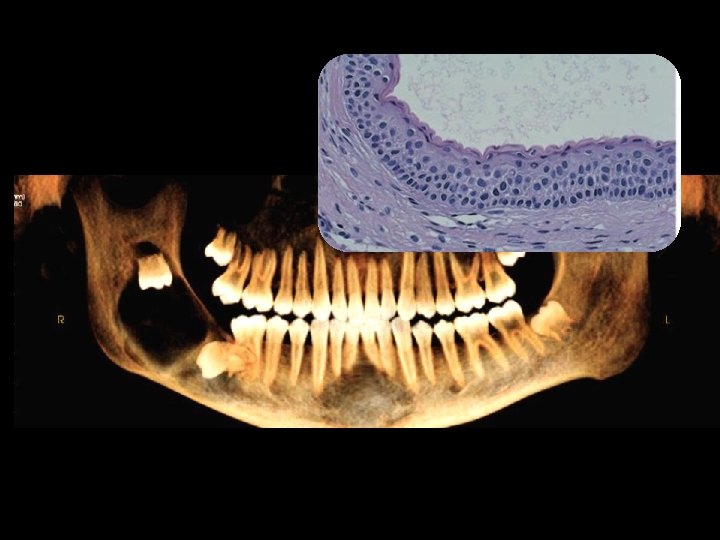

CBCT